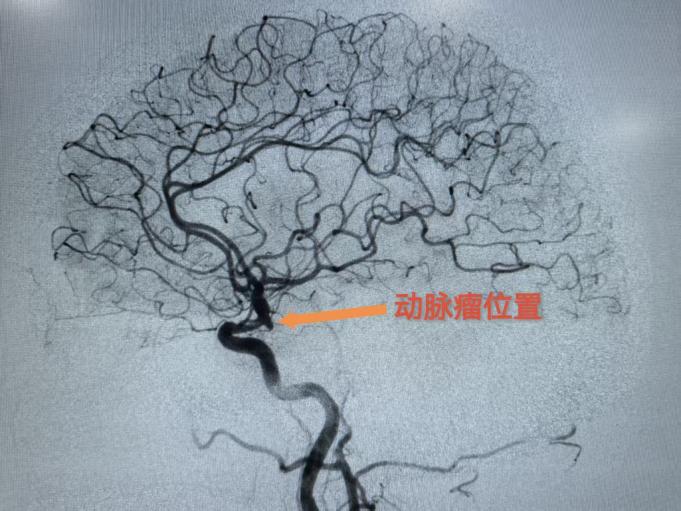

76岁的王女士5年前开始出现不明原因的头晕,时轻时重,休息后可缓解,她以为是“年纪大了难免的毛病”,未正规检查。直到一周前,头晕突然加重,看东西天旋地转,连下床走路都需要家人搀扶,这才急忙到医院就诊。头颅CT检查提示“多发性脑梗死”,进一步头颅MRI+MRA检查后,医生发现了一个隐藏的“定时炸弹”——左侧颈内动脉C7段动脉瘤,大小约5.2mm×4.8mm,瘤颈宽3.0mm。结合她180/110mmHg的高血压病史,医生诊断为“左侧颈内动脉C7段动脉瘤、多发性脑梗死、高血压病3级(极高危)”,建议尽快手术治疗。

颈内动脉C7段位于颅内动脉虹吸部远端,邻近大脑中动脉和大脑前动脉分叉处,血流冲击力大,一旦破裂可导致蛛网膜下腔出血,致死致残率极高。王女士的动脉瘤属于“宽颈动脉瘤”(瘤颈>4mm或瘤颈/瘤体>1/2),就像一个瓶口宽大的气球,直接填入弹簧圈容易“漏出”,复发率高。

经过神经外科团队讨论,为王女士制定了支架辅助弹簧圈栓塞术方案。该方案的核心原理是,首先在动脉瘤的开口处(即瘤颈)植入一枚支架,这枚支架如同“栅栏”一般,既能有效阻挡后续填入的弹簧圈脱落至正常血管,又能通过改变动脉瘤区域的血流方向,促进瘤腔内血栓的形成;随后,通过微导管将柔软的铂金弹簧圈精准送入动脉瘤腔内,逐步填充并闭塞瘤腔,从而从根本上消除动脉瘤破裂的风险。术后造影显示动脉瘤100%栓塞,支架通畅,无血管痉挛或出血,手术顺利结束。